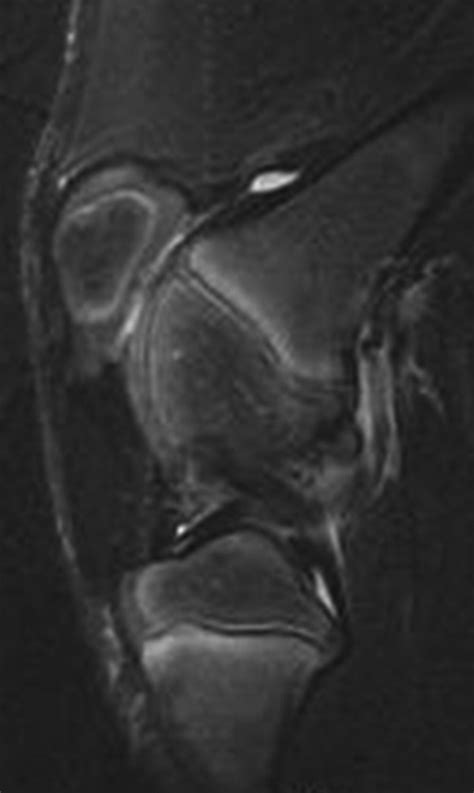

• Imaging Tests: X-rays, MRI, or CT scans may be used to visualize the bone and surrounding tissues. MRI is particularly useful for detecting bone contusions.